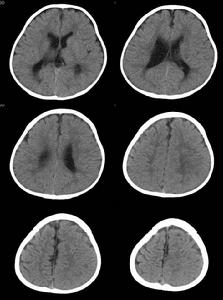

2.影像學 終末期肺炎由於症狀、體徵不明顯,故診斷主要依據X 線,多顯示小片狀陰影,沿支氣管走行,右下肺為著,但臨床上也可聽到肺部可聞及明顯的水泡音,而胸片炎症徵象不明顯者,可能與長期臥床、炎性分泌物積聚到脊柱旁導致炎症陰影顯示不清有關。除此以外如合併心衰可見心影增大,並可見胸腔積液徵象,其原因考慮由於胸膜炎症反應,低蛋白血症及心衰綜合因素所致。